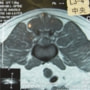

■ MRI検査

第5-6腰椎間で右側神経根が腫大し、脊柱管内に連続した腫瘤病変が認められました。脊髄および馬尾神経は右側から重度に圧迫されていました。

MRI検査所見

MRI 1

MRI 2